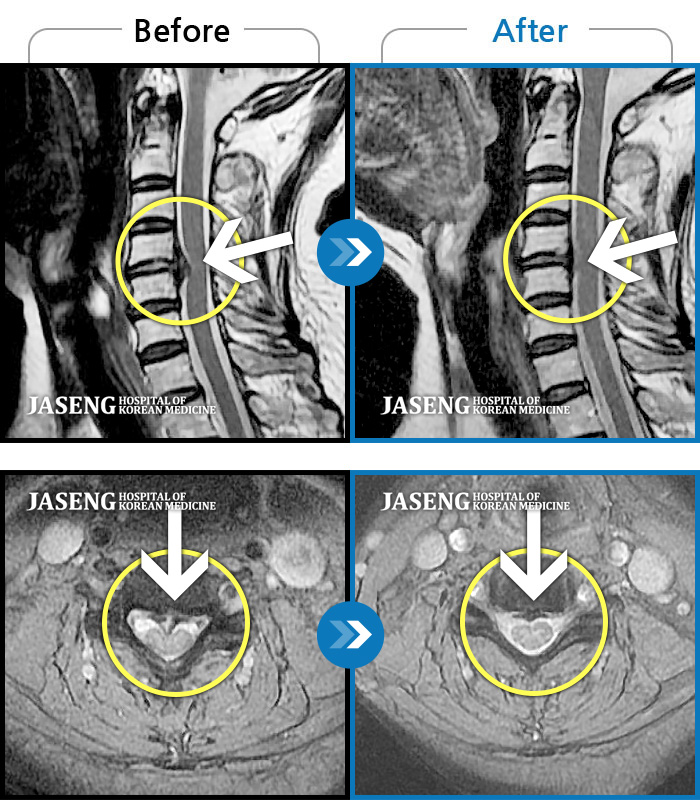

- MRI ġ

MRI ġ

1,293 MRI ũ ʸ Ȯϼ.